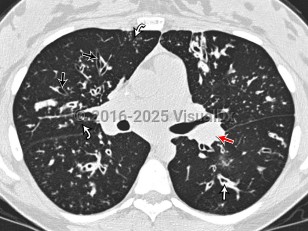

Cystic fibrosis is a congenital metabolic disorder caused by a mutation in a protein that regulates chloride ion transport. This leads to viscous secretions and eventual dysfunction of exocrine glands, most notably affecting the lungs and pancreas. Symptoms usually appear in childhood and include recurrent pulmonary infections with gradual loss of pulmonary function and pancreatic insufficiency leading to poor weight gain. Liver involvement can range from steatosis to advanced cirrhosis with portal hypertension.

Pseudomonas aeruginosa, Staphylococcus aureus, and Mycobacterium abscessus infections are complications of cystic fibrosis. Patients with cystic fibrosis may be anemic. Patients often have impaired absorption in the small bowel and ciliary dysfunction in the genitourinary system that can impact fertility.